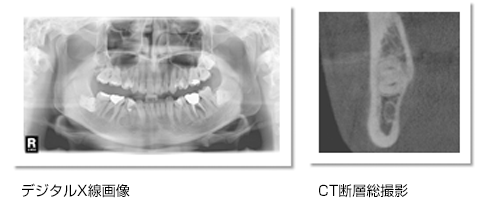

安東歯科医院では、レントゲン撮影においてデジタルX線撮影装置を導入しています、従来のX線写真の 1/10の放射線量で撮影可能で、身体への影響を最小限度にできます。また、撮影して瞬時にコピュータに映し出せる為に、お待たせする時間も短縮できました。

下顎骨の幅、下顎管までの長さを正確に測定できるため、的確なサイズのインプラントを安全に埋入できます。